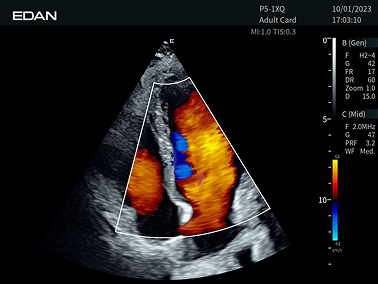

Imágenes Clínicas